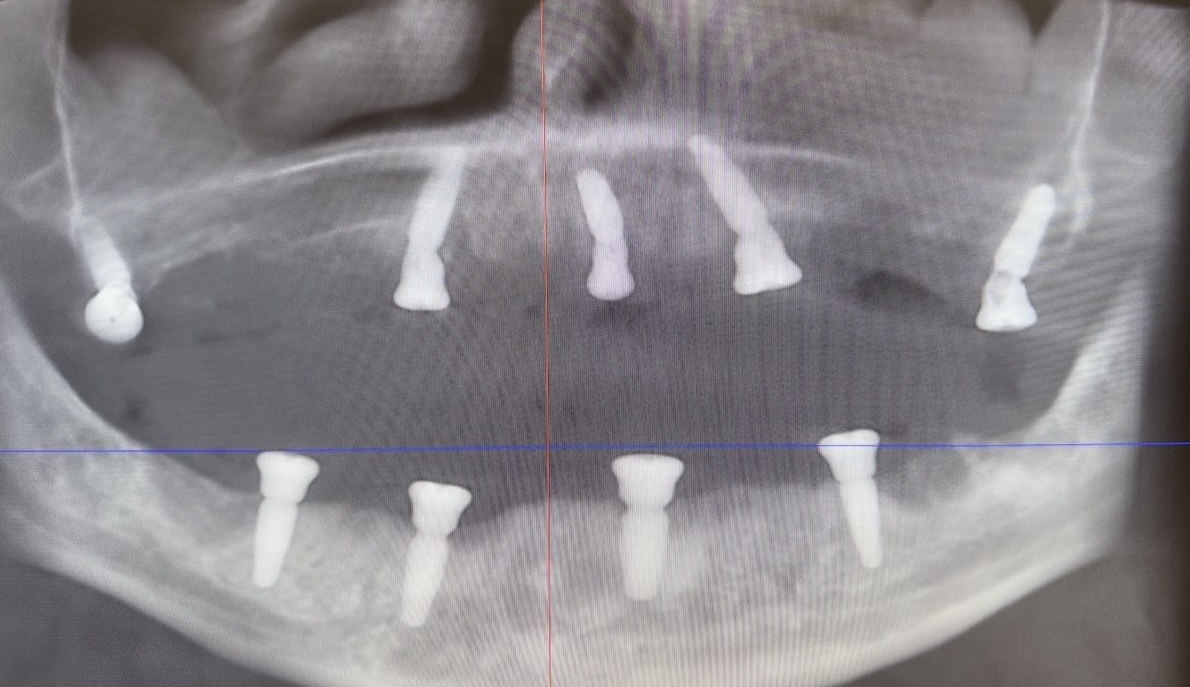

All-on-4 на обе челюсти за 8 дней с имплантатами Megagen

Описание случая

Пациент обратился для комплексного протезирования зубов верхней и нижней челюсти.

В связи с небольшим объемом костной ткани было решено проводить имплантацию зубов по методике все-на-4. На верхней и нижней челюсти было одновременно проведено протезирование на имплантатах временными конструкциями. Через 6 месяцев можно устанавливать постоянные протезы.

В работе были использованы корейские имплантаты Megagen. Для имплантации зубов в Минске пациенту потребовалось 8 дней.